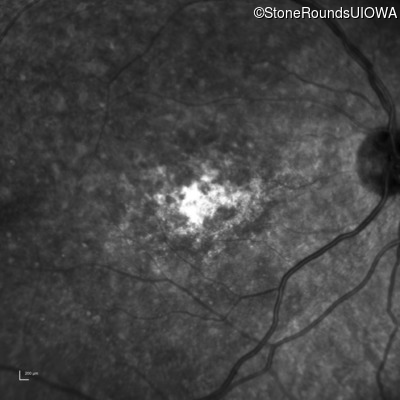

Infrared Fundus Photograph - Right - 20/400 sc

Exemplar

Infrared Fundus Photograph - Left - 20/150 sc